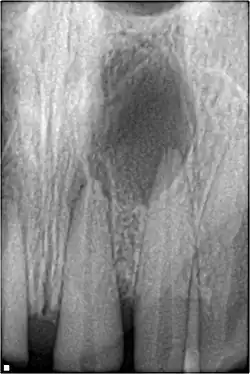

An odontogenic infection is an infection that originates within a tooth or in the closely surrounding tissues.[1] The term is derived from odonto- (Ancient Greek: ὀδούς, odoús – 'tooth') and -genic (Ancient Greek: -γενής, -γενῶς; -genḗs, -genôs – 'birth'). The most common causes for odontogenic infection to be established are dental caries, deep fillings, failed root canal treatments, periodontal disease, and pericoronitis.[2] Odontogenic infection starts as localised infection and may remain localised to the region where it started, or spread into adjacent or distant areas.

It is estimated that 90–95% of all orofacial infections originate from the teeth or their supporting structures and are the most common infections in the oral and maxilofacial region.[3] Odontogenic infections can be severe if not treated and are associated with mortality rate of 10 to 40%.[4] Furthermore, about 70% of odontogenic infections occur as periapical inflammation, i.e. acute periapical periodontitis or a periapical abscess.[3] The next most common form of odontogenic infection is the periodontal abscess.[3] Despite being more common in underprivileged regions, odontogenic infections affect people from all over the world, even in developed countries.[5]